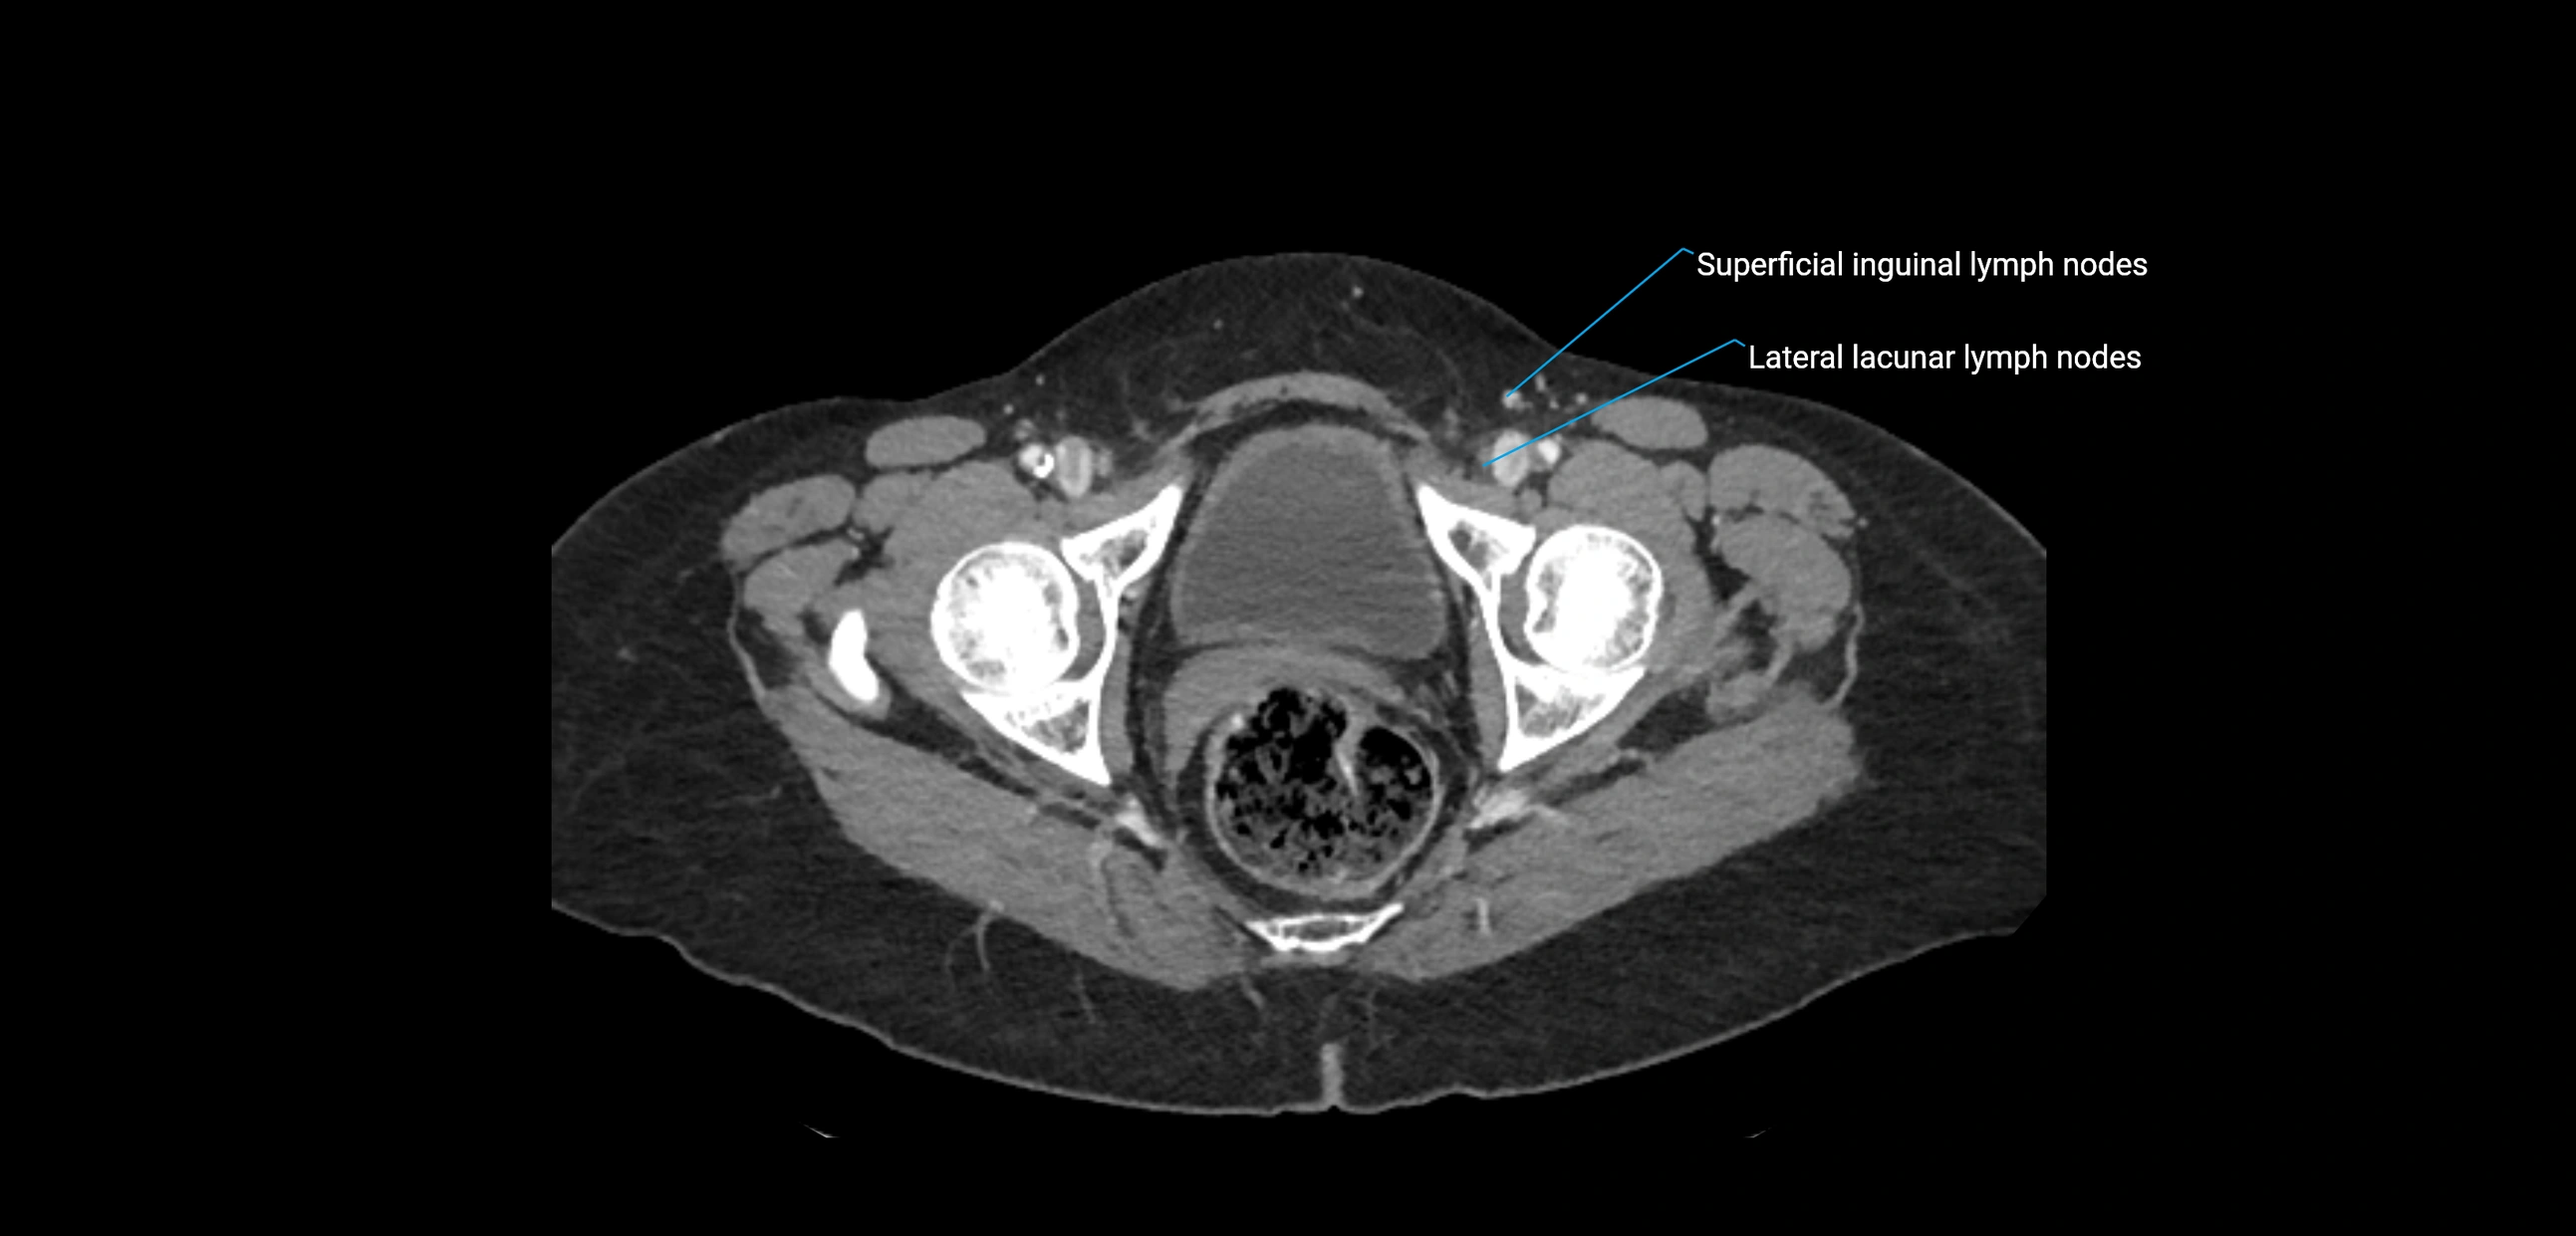

CT Appearance

CT Pre-Contrast:

• Nodes appear as soft-tissue density nodules adjacent to the aorta and IVC

• Calcification may be seen in chronic infections (e.g., tuberculosis)

CT Post-Contrast:

• Normal nodes enhance homogeneously

• Malignant nodes may show heterogeneous enhancement, central necrosis, or conglomerate formation

• Size >1 cm short axis is suspicious, though morphology and distribution are equally important